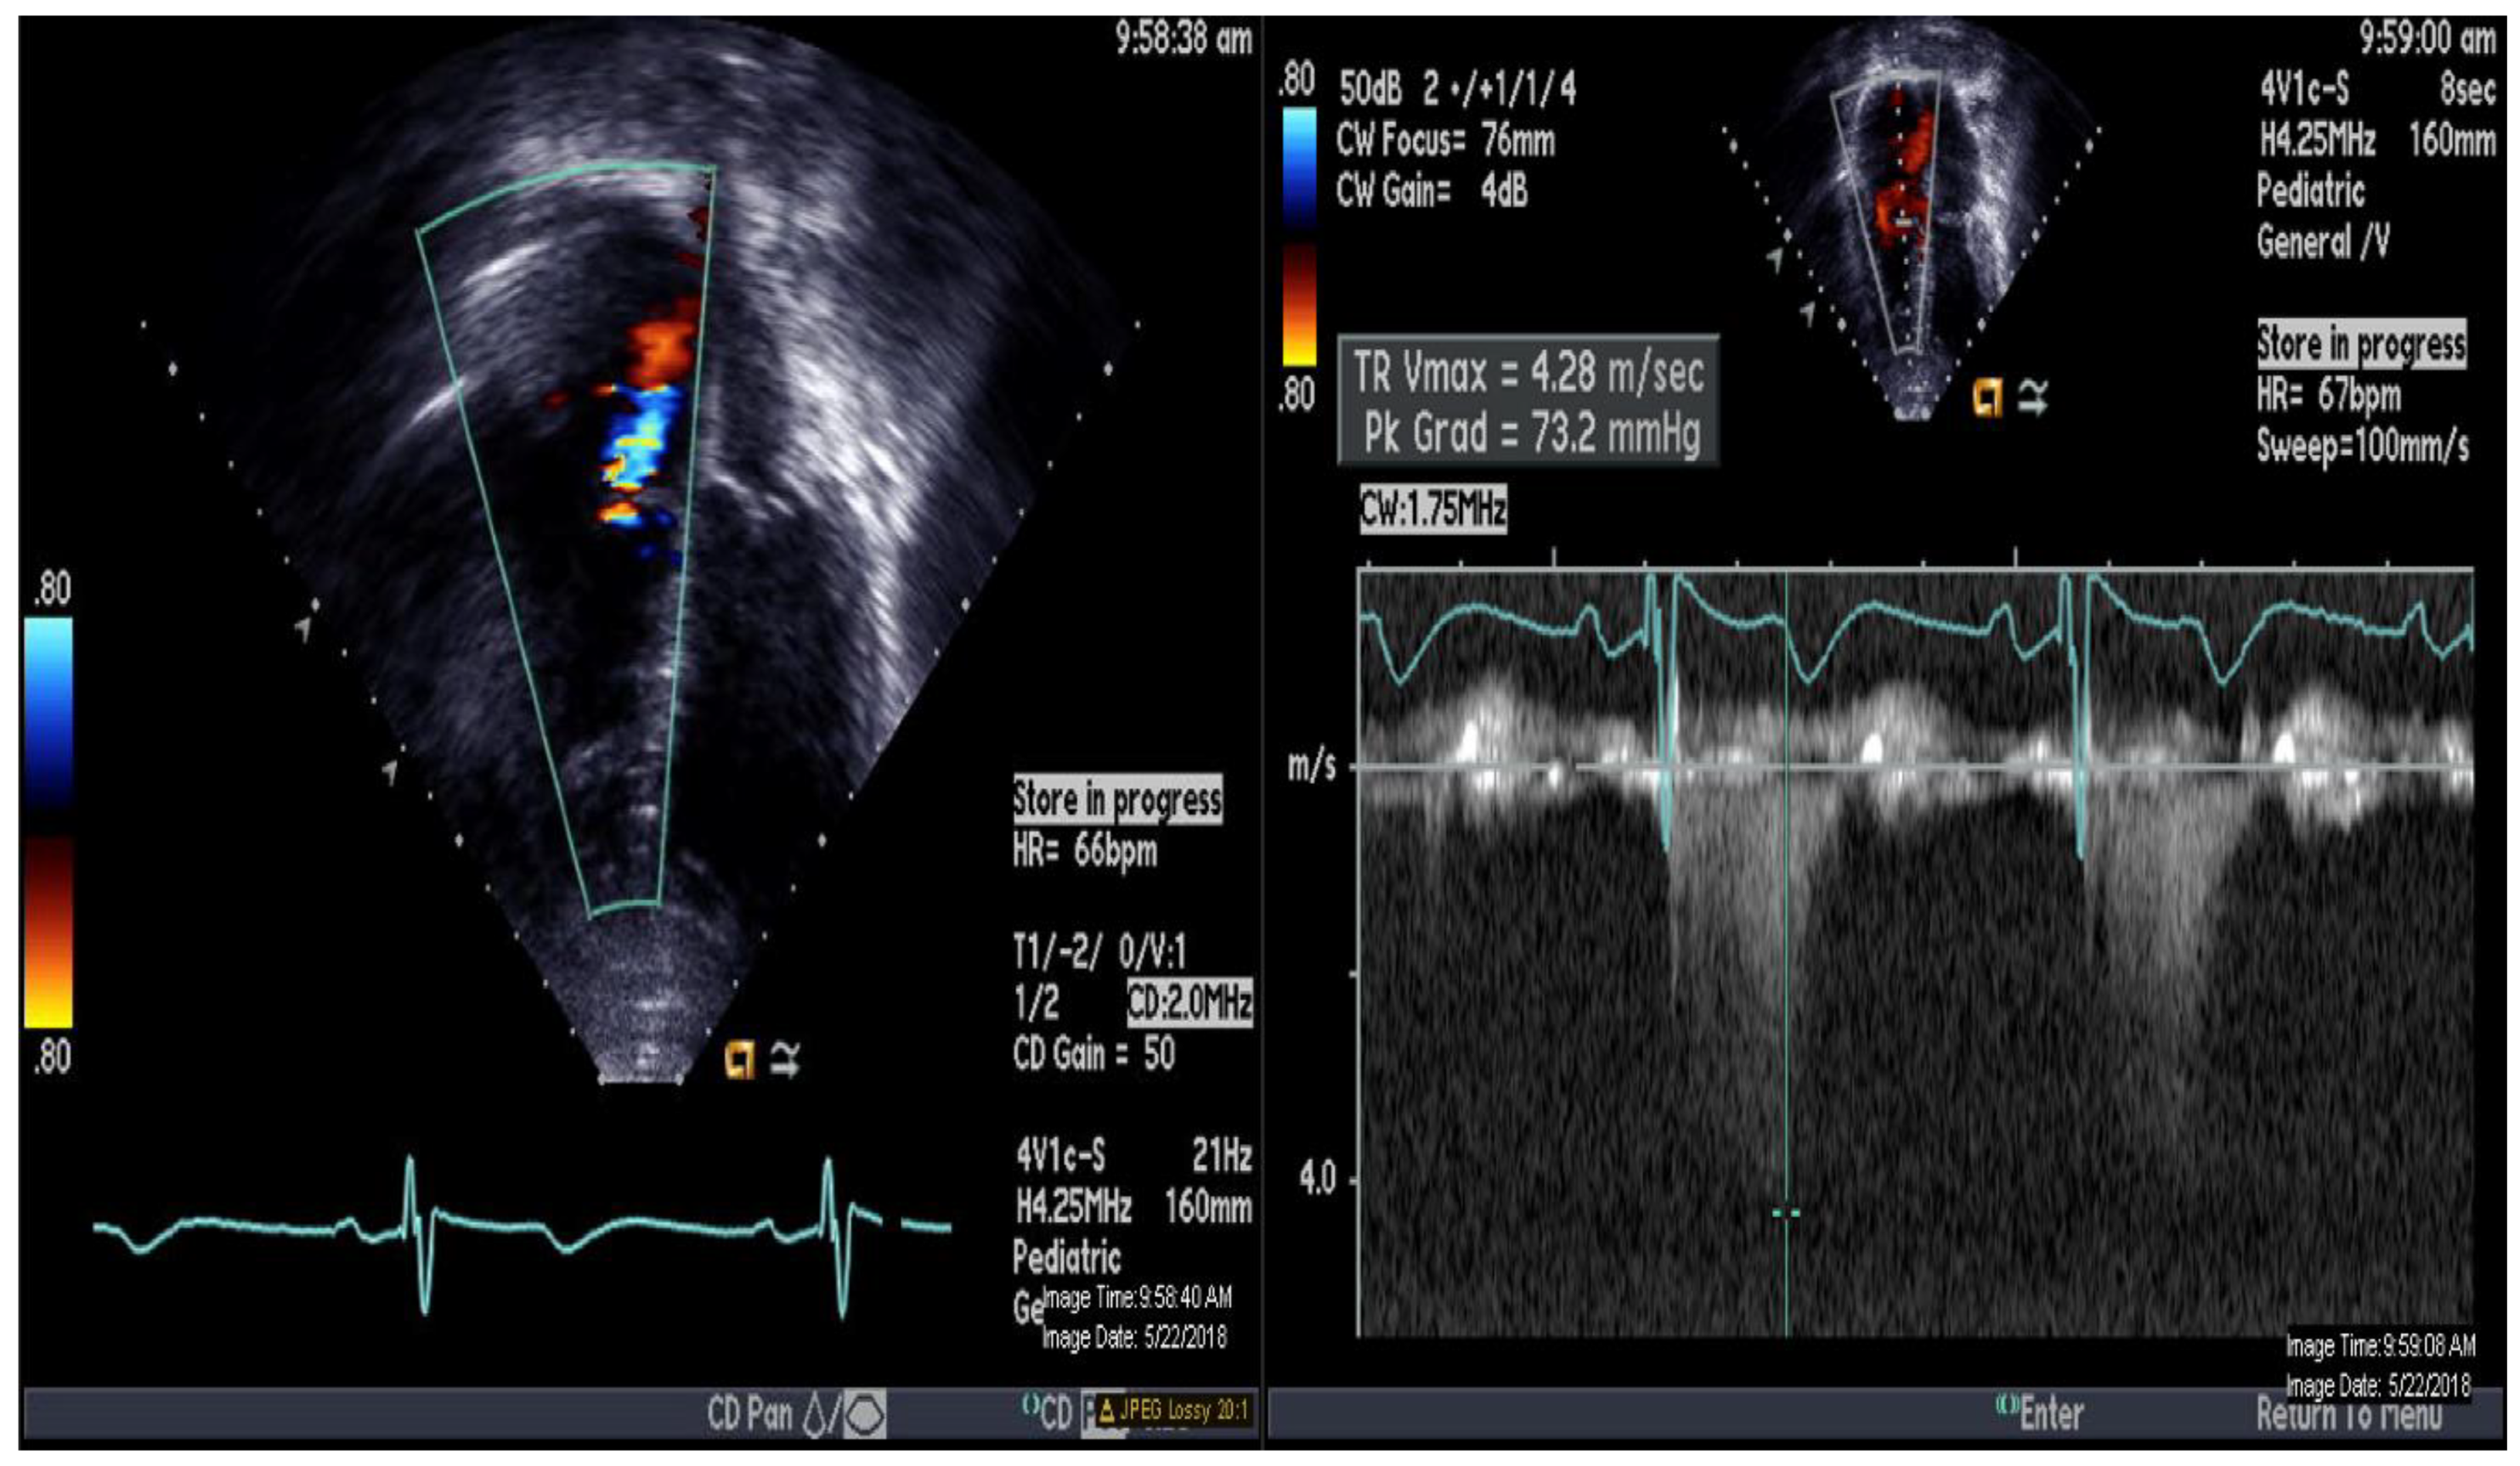

| PAP mm Hg (mean) | 79/43 (57) | 90/46 (66) |

| AoP mm Hg (mean) | 78/43 (59) | 97/46 (65) |

| PVRi Wood U m2 | 10.4 | 9.4 |